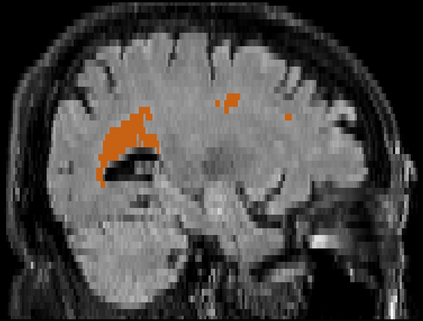

Brain atrophy and white matter hyperintensity (WMH) are critical neuroimaging features for ascertaining brain injury in cerebrovascular disease and multiple sclerosis. Automated segmentation and quantification is desirable but existing methods require high-resolution MRI with good signal-to-noise ratio (SNR). This precludes application to clinical and low-field portable MRI (pMRI) scans, thus hampering large-scale tracking of atrophy and WMH progression, especially in underserved areas where pMRI has huge potential. Here we present a method that segments white matter hyperintensity and 36 brain regions from scans of any resolution and contrast (including pMRI) without retraining. We show results on six public datasets and on a private dataset with paired high- and low-field scans (3T and 64mT), where we attain strong correlation between the WMH ($\rho$=.85) and hippocampal volumes (r=.89) estimated at both fields. Our method is publicly available as part of FreeSurfer, at: http://surfer.nmr.mgh.harvard.edu/fswiki/WMH-SynthSeg.